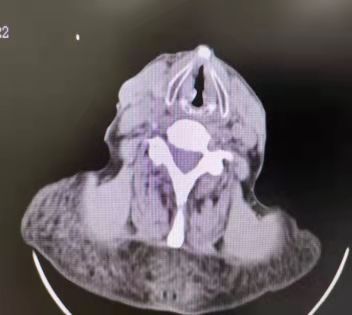

患者,男,77歲,氣短、咳嗽,慢阻肺、高血壓病史多年。肺功能?chē)?yán)重受損,稍活動(dòng)即感呼吸困難。因聲音嘶啞就診我市知名三甲醫(yī)院,診斷“聲帶腫物”,因重度肺功能損害不能耐受手術(shù)麻醉。為求確診慕名前來(lái)我院耳鼻喉科就診。經(jīng)頸部CT檢查提示:“右側(cè)聲帶新生物”。不論其良、惡性腫瘤,手術(shù)切除是根除手段。

在充分評(píng)估支氣管鏡檢查風(fēng)險(xiǎn)后,首先在局麻下行電子支氣管鏡檢查:右側(cè)聲帶前中1/3可見(jiàn)腫瘤組織致喉狹窄。活檢組織病理證實(shí)為“高分化鱗癌”。因家屬有強(qiáng)烈的治療愿望,孫主任組織全科再次評(píng)估麻醉手術(shù)風(fēng)險(xiǎn)。患者重點(diǎn)、難點(diǎn)在于高齡,術(shù)中麻醉風(fēng)險(xiǎn)高,容易出現(xiàn)麻醉意外事件,難以耐受聲帶腫瘤切除并重建手術(shù)。隨后及時(shí)